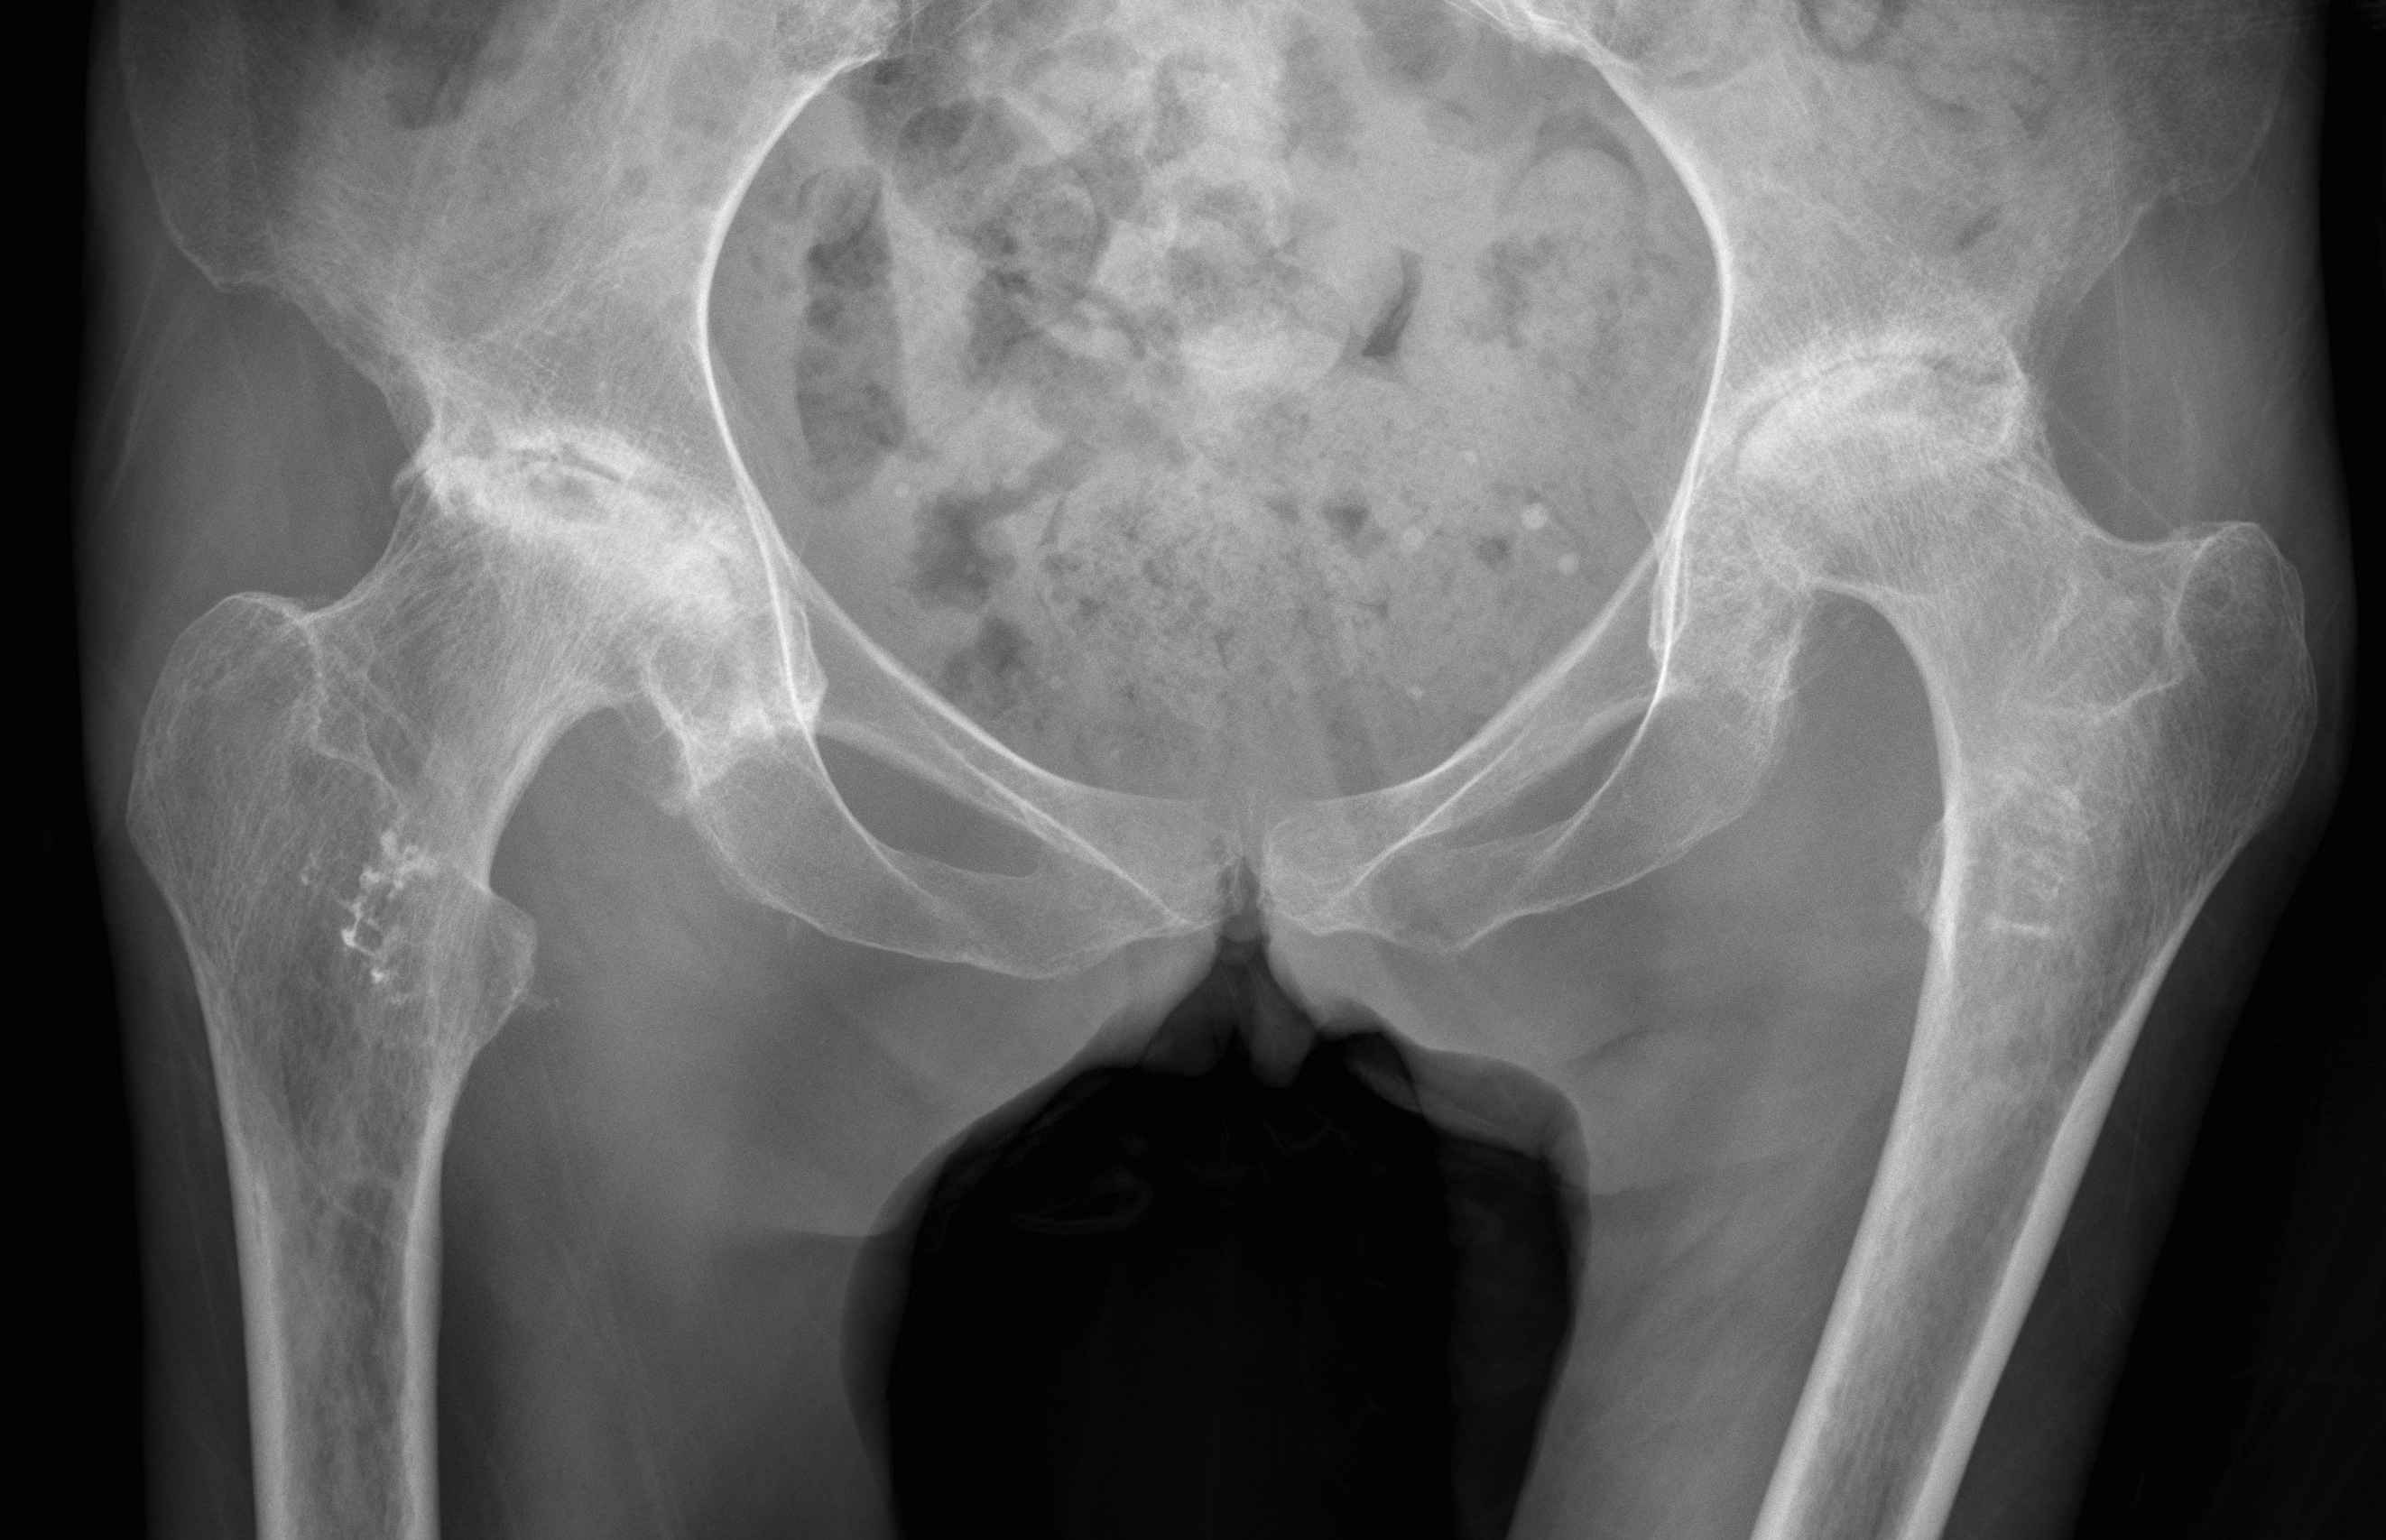

Etiology

Primary OA: 50%

Secondary OA: 50%

Secondary OA

SUFE Perthes

DDH Protrusio

Trauma

Paget's AVN

Sepsis

FAI